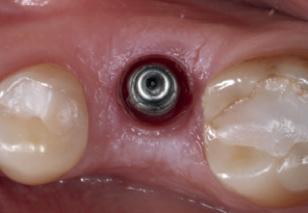

To achieve good primary closure, it was decided to modify the procedure and trim the roots up to the furcation to ensure a sound collar of alveolar bone and advance the buccal flap. This modification helped significantly during primary closure of the socket. LL8 tooth was removed completely as the roots became loose as well as UR8 and LU8. The post-operative phase was uneventful, and she recovered well (Fig 4).

Implant prosthetics and dental prosthetics differ considerably, with the absence of periodontal ligament in the implant/ prosthesis complex. This situation causes mechanical problems to the implants, especially to the implant prosthetic material, due the lack of stress absorption resulting from the normal impact during chewing (1) (2). Among the problems we face in daily practice is the unscrewing and fracturing of veneering material of the implant crown and fracturing of implant/ abutment components.

During daily practice, it is very common to face situations where the implant has to be placed lingually due to normal resorption (Fig. 1) of the buccal plate after the extraction. But, at the same time, it is not necessary to perform bone grafting procedures. The result of this scenario is to increase the stress on the implant-bone complex when we use rigid materials like conventional ceramics (Fig. 2).

For this daily practice situation, the combination of rigid and resilient materials against the antagonist, allows the stress to the implant-bone complex to be reduced (Fig. 3,4).